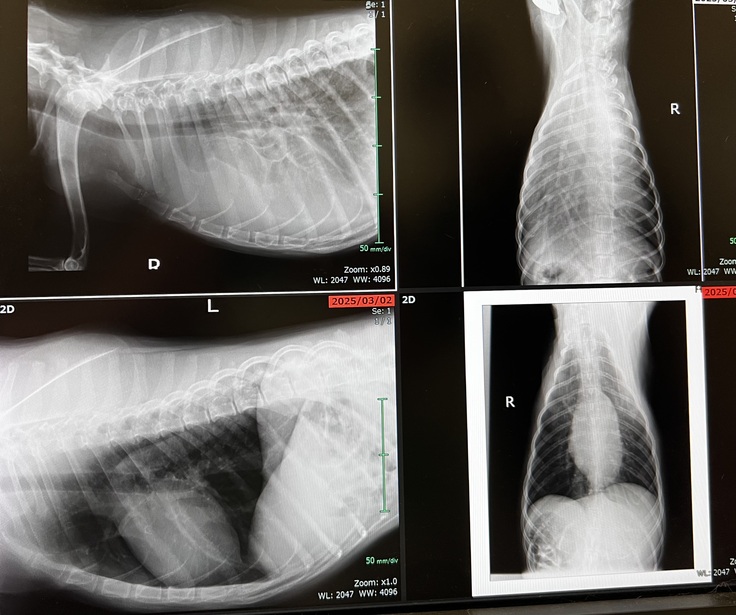

肺に転移が見つかりました

3月頭に撮影したレントゲンとは

明らかに違い、素人でもわかるくらい

真っ白な肺でした。

癌が肺に転移していて

その影響で水が溜まっているとのお話でした。